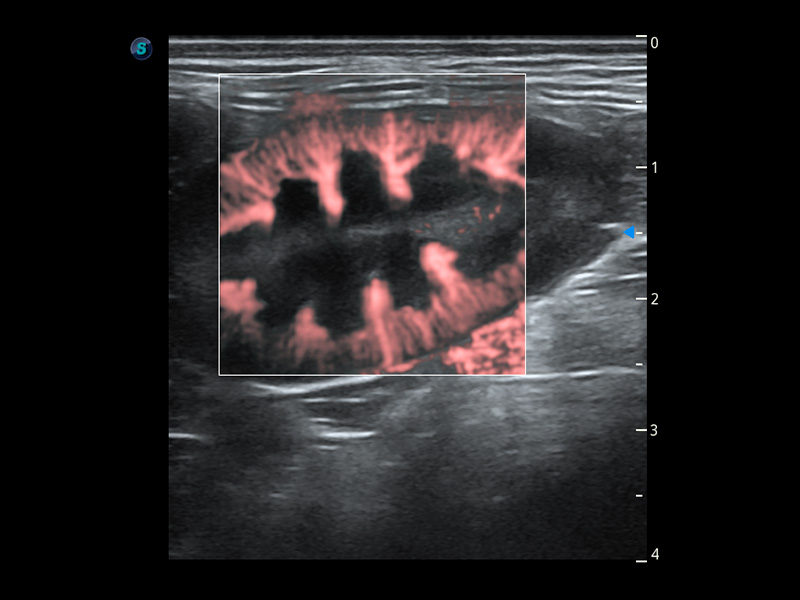

SR Flow 高分辨率血流成像

能夠清晰顯示細(xì)小、低速血流圖像,獲取傳統(tǒng)彩色多普勒技術(shù)難以得到的細(xì)節(jié)和信息。

(犬)腎臟血流